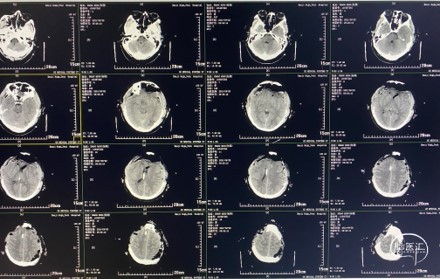

术后复查头颅CT(术后第1天)

20头颅CT提示:双侧额叶减压充分,术区未见明显出血,侧脑室引流管在位。